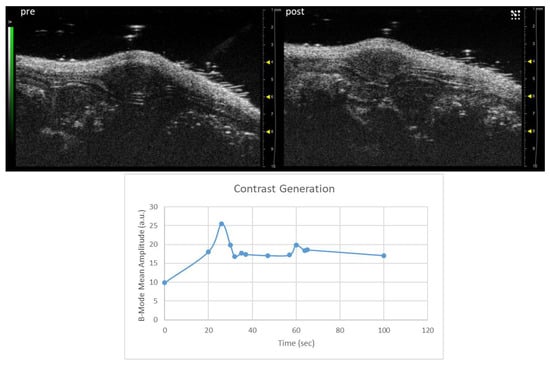

3.5. US imaging Detection of the Theranostic Nanobubbles